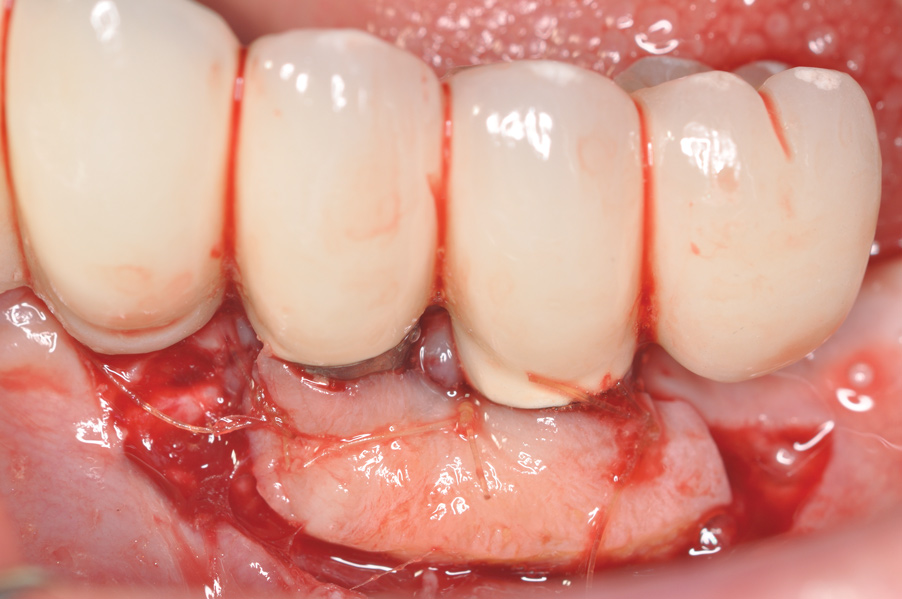

A thinner gingival biotype is also a sign that the underlying bony housing may be thin; this relates to the concept of blood supply to maintain bone height. In thinner bone that is subjected to inflammation, adequate blood supply may not be present to maintain its viability. Where gingiva is thin or absent at the time of implant placement, strong consideration must be given to proactively grafting these sites with soft tissue just prior to restoration or at the earliest signs of inflammation to protect the underlying bone. Figure 8 through Figure 12 highlight such a situation.

Fig 8. A mucogingival deformity existed on the premolar implants.

Figure 8

Fig 9. A full-thickness flap was elevated and the surfaces decontaminated with air-powder abrasion with glycine-based powder and citric acid.

Figure 9

Fig 10. An autologous subepithelial connective tissue graft was secured in the area with 6-0 chromic gut suture using an interrupted technique. Recombinant platelet-derived growth factor was applied to both the implant surfaces and the graft.

Figure 10